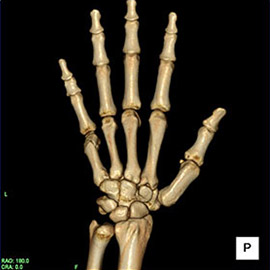

80列マルチスライスCTで撮影した画像

整形